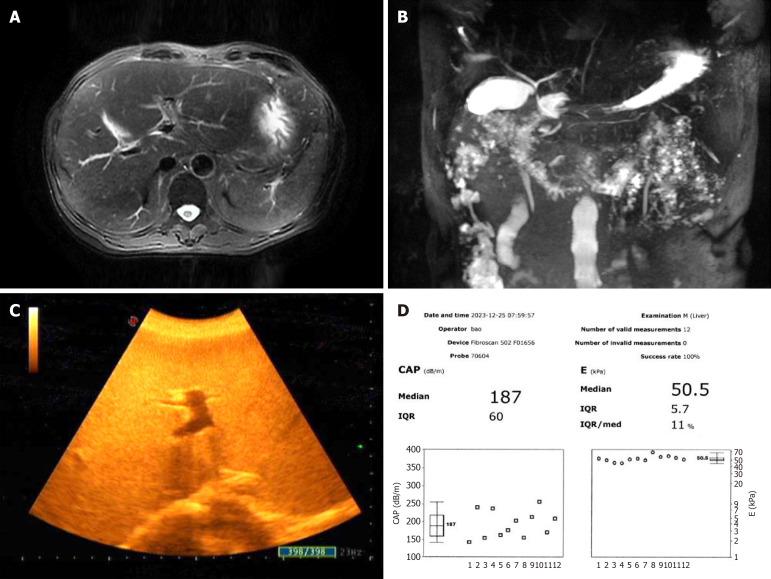

A 62-year-old man was admitted with persistent liver dysfunction of unknown cause and poor treatment outcomes. His condition persisted, and he developed chronic liver failure, with severe cholestasis in the later stage that was gradually accompanied by renal injury. Ultimately, he was diagnosed with hepatic amyloidosis through liver biopsy and pathological examination.

Hepatic amyloidosis rarely occurs in the clinic, and liver biopsy and pathological examination can assist in the accurate and effective diagnosis of this condition.